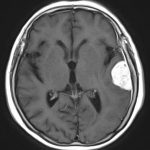

図1 さまざまな部位に発生した髄膜腫のMRI画像所見

脳の表面近くに発生した髄膜腫